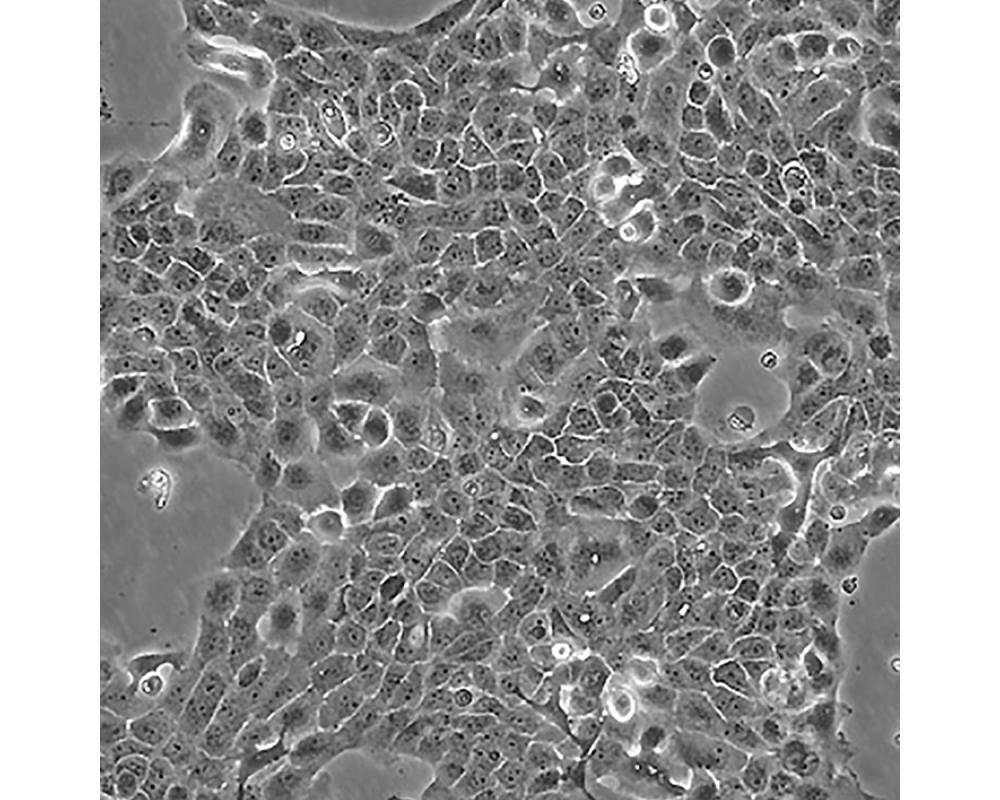

A-431(A431,A 431)

中文名稱 人皮膚鱗癌細(xì)胞

組織來(lái)源 外陰鱗狀細(xì)胞癌;女性

細(xì)胞種屬 Homo sapiens, human

生長(zhǎng)特性 adherent

形態(tài)特征 epithelial

細(xì)胞描述 該細(xì)胞源自一位患有皮膚鱗狀細(xì)胞癌的85歲女性,是GiardDJ等人建立的一系列細(xì)胞株中的一株。該細(xì)胞在免疫抑制小鼠體內(nèi)可成瘤,在瓊脂上培養(yǎng)可形成克隆;是一個(gè)超三倍體人細(xì)胞株。